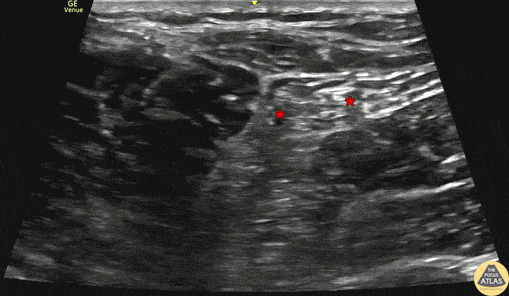

40s M presented with a laceration to the lateral lower leg after jumping through a window. To facilitate laceration irrigation and repair, a sciatic nerve block was performed at the popliteal fossa. The patient was placed in the contralateral decubitus position, and the linear probe was placed in the popliteal fossa in a transverse orientation to identify the sciatic nerve just proximal to the bifurcation into tibial and common peroneal nerves. This image shows the nerve block, with the needle entering from the lateral aspect, depositing anesthetic within Vloka’s sheath which surrounds the sciatic, tibial, and common peroneal nerves at the bifurcation. The block was performed just at the level of the bifurcation, and the tibial and common peroneal nerves are marked by the red asterisk (*) here. The patient had relief of pain, and the irrigation and laceration repair were able to be performed without any additional local anesthetic. Dr. Rachel Vanderwel, PGY3, and Dr. Michael Heffler, PGY4 Denver Health Residency in Emergency Medicine